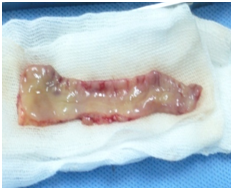

Figure 3B Buccal mucosa graft after harvesting.